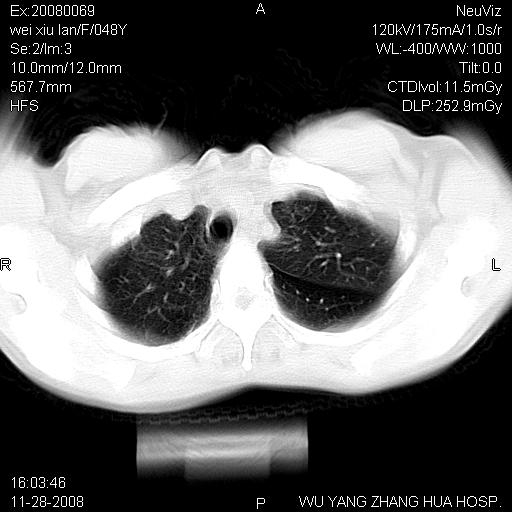

标题: CT16847:女,48岁,咳嗽,发热两日,平常偶有上腹部不适。 [打印本页]

标题: CT16847:女,48岁,咳嗽,发热两日,平常偶有上腹部不适。

能否考虑食管裂孔疝?请老师们多多指教。

这个是左侧膈膨升伴不完全性胃翻转,手术将松弛的左横膈膜折叠缝合即解决问题。

支持左侧膈疝,心脏受压右移.

左下肺不张、膈膨升,胸腔胃

1.左侧隔膨升

2.左下肺炎性改变

胃、脾脏及部分肠管明显升高,并压迫心脏移位,

首先考虑:左侧膈疝。

左侧胸腔内见胃肠及脾脏影

支持膈疝

左膈顶及肋膈角均上移,膈面光滑,考虑左膈肌麻痹